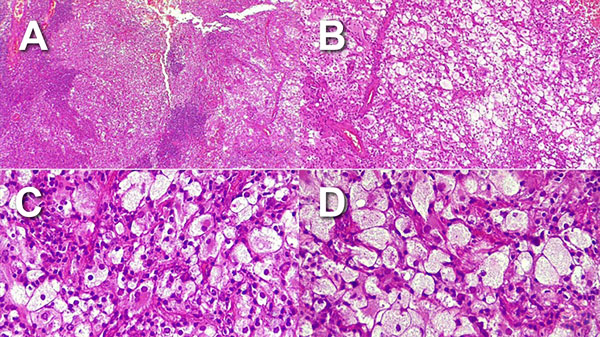

Citología: líquido intratumoral con fondo proteínico con hemorragia leve. Se observan elementos celulares aparentemente histiocitarios de citoplasmas amplios vacuolados y células xantomizadas, se acompañan de células sueltas plasmáticas y linfocitos.

Histopatología: tumor intraaxial temporal compuesto por una población celular heterogénea: células de citoplasmas, amplios claros xantomizados con discreto pleomorfismo nuclear (Figura 3A), alternado con células de menor tamaño con núcleos excéntricos y nucléolos conspicuos (Figura 3B), así como linfocitos y células plasmáticas formando agrupaciones alrededor de la lesión (Figuras 3C y 3D).

Figura 3. Histopatología con coloración de hematoxilina y eosina.